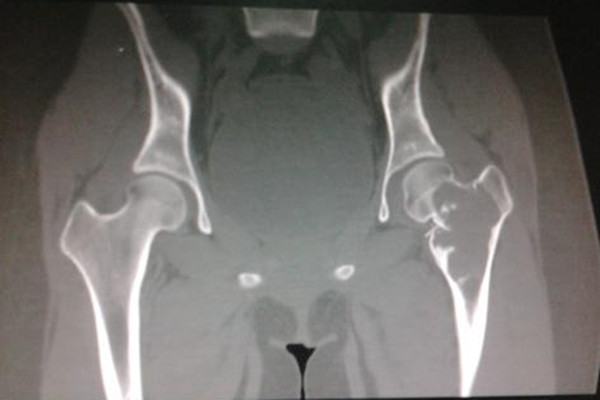

苏兰市联盟村九社发现了一个没有身份的男童尸体,这个孩子大概六岁到八岁,身高106厘米,上身穿着一个短袖t恤,下身穿着一个七分裤,然后穿了一双蓝色的运动鞋。民警介绍,这个男孩子有陈旧性的骨折,具体原因还在调查,一个六七岁的孩子,身体就有了,陈旧性的骨折,如果是往坏了想,简直不敢想象。